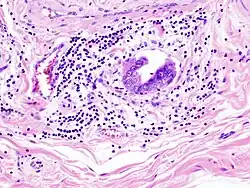

Invasão linfática de adenocarcinoma na vesícula biliar capturada numa histopatologia -

Histopatologia de um adenocarcinoma da vesícula -